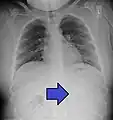

A coin seen on lateral CXR in the esophagus